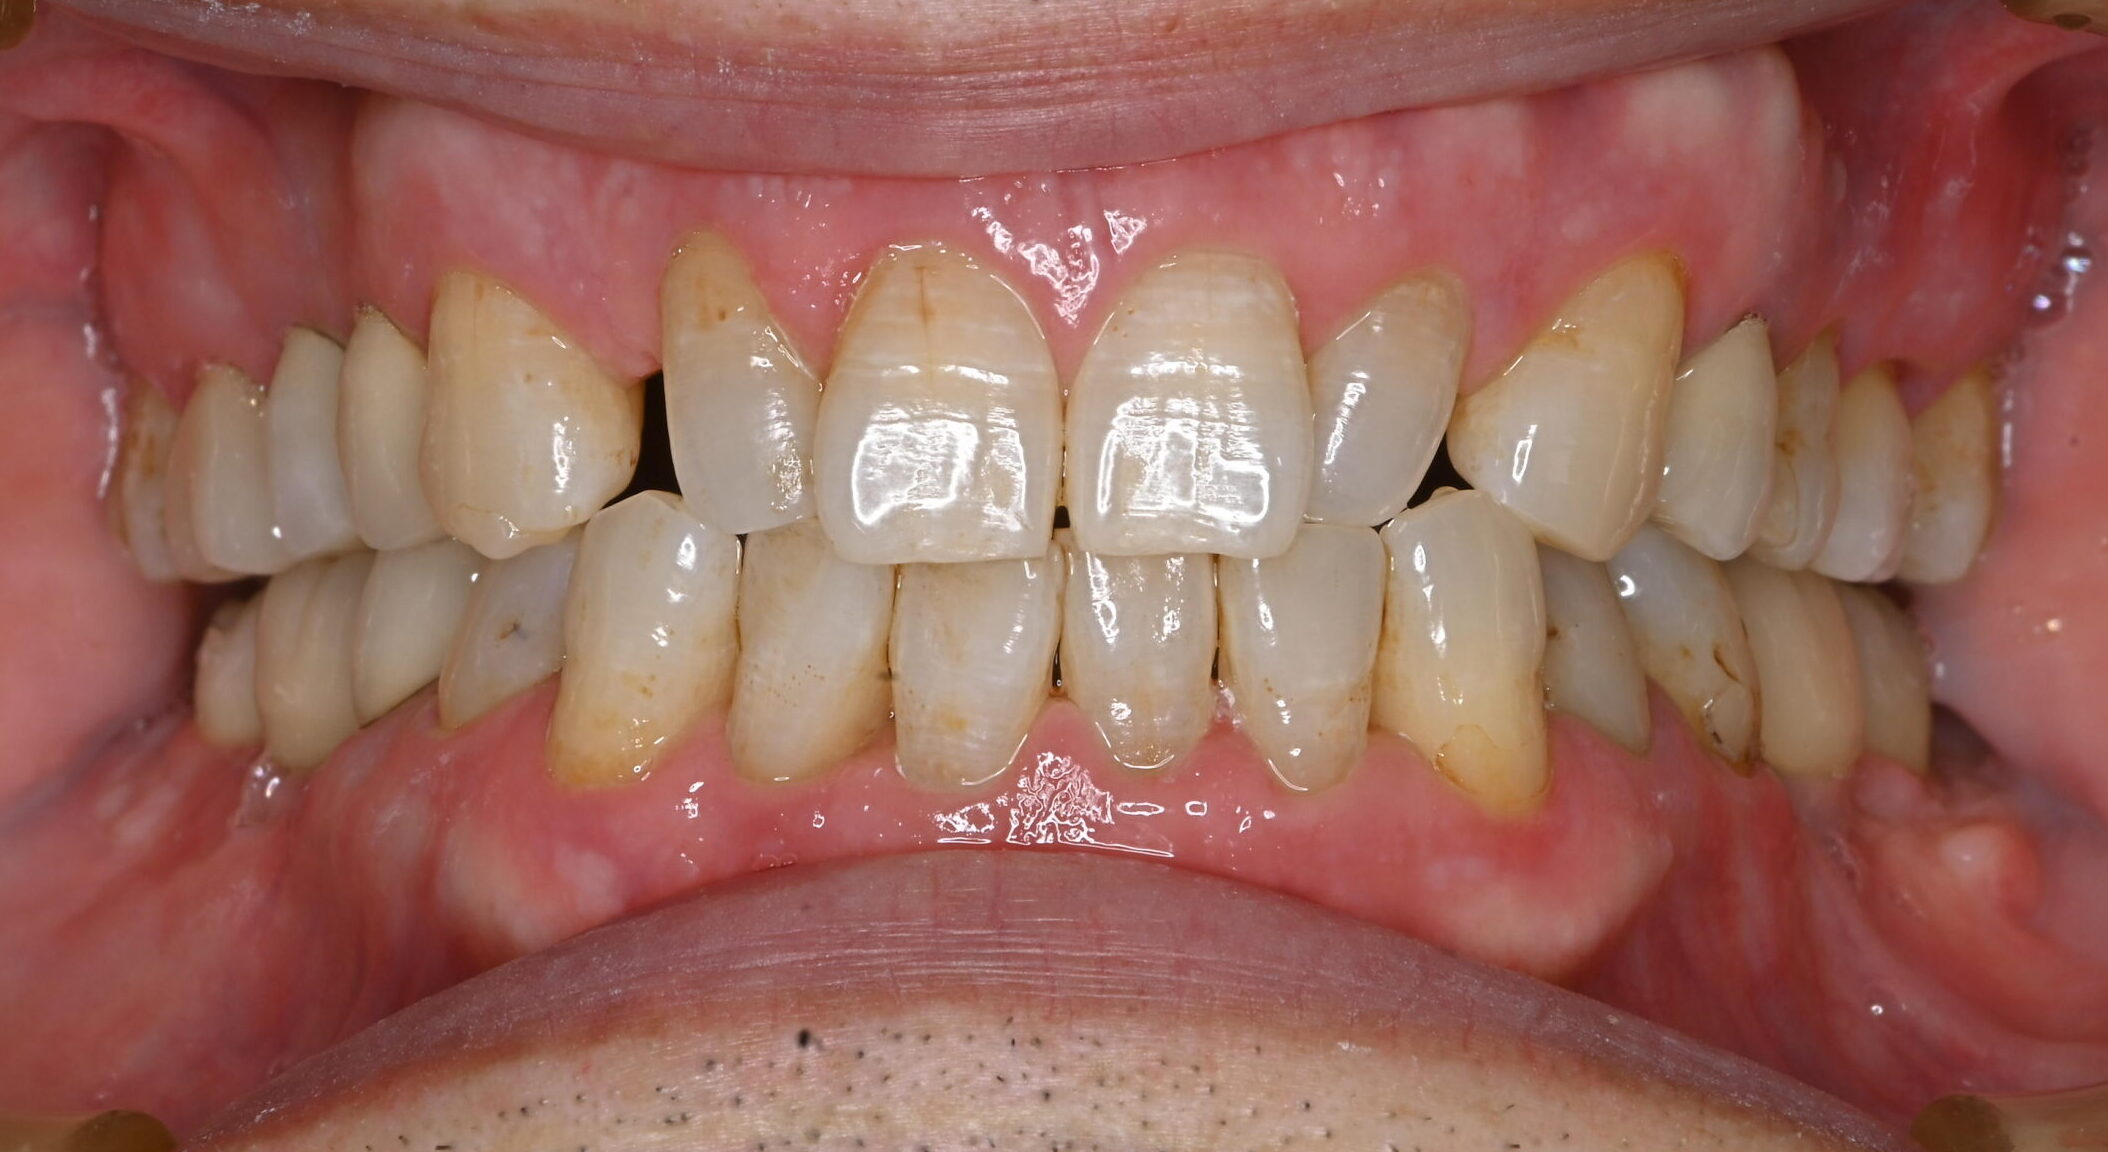

after

治療後

症例写真 after

まず右下6番の抜歯、インプラント埋入手術、上部構造の装着を行い、次いで左下6番の治療を右下同様に進めました。

上部構造装着後10年以上経過しますが、定期的なメインテナンスと患者さんの日々のケアの甲斐あって、現在まで良好な経過をたどっています。